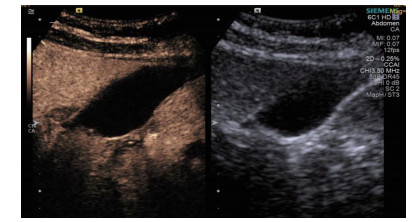

| 图 3 经引流管造影胆囊超声显像,二维图像(左),造影图像(右) |

术后再次经肘静脉超声造影同时经引流管超声造影:PTGBD后,再次经肘静脉快速团注SonoVuel 2 mL,在造影成像模式下进行观察肝脏被膜、胆囊床穿刺路径有无造影剂外渗,腹腔内有无外渗凝聚的造影剂,判断有无活动性出血及出血程度,如判断出血速度快、出血量较大,考虑动脉性出血,及时改为开腹或腔镜手术止血。PTGBD术后经引流管超声造影,置管成功后快速抽出胆囊内残留胆汁,减轻胆囊压力后,在超声造影模式下直接经引流管注入配制待用的稀释声诺维造影剂20 mL,实时动态的观察造影剂在胆囊腔内的充盈范围(图 2、3),评估引流管的通畅程度及引流范围、观察其在胆囊腔内的位置走形及卷曲情况、观察胆囊周边及腹腔内有无造影剂外渗。如患者腹痛症状加剧,结合经引流管超声造影判断有胆汁漏出表现,应持续监测观察患者生命体征及保守治疗效果,必要时及时改行开腹或腔镜手术治疗。

超声造影是利用超声造影剂微泡(本组应用的是声诺维超声造影剂微泡)在低机械指数声波照射下发生共振,产生线性及非线性谐波回声信号,形成造影增强图像的技术,是近年来新兴的超声技术,具有实时、可连续观察、无辐射、可重复性好、毒不良反应少等优势,为临床提供了全新的诊疗手段[14]。经肘静脉注入的标准配置超声造影剂是一种血池造影剂,可以反映组织的血流灌注情况同时亦被广泛应用于肝、脾、肾等实质性脏器破裂的诊断,其诊断的敏感性及特异性均明显优于二维超声,且与增强CT有较好的一致性[15-16]。本组病例术前经肘静脉注入标准配置造影剂后,胆囊壁均显影增强,胆囊穿孔及周边积液处表现为造影无充盈区,穿刺置管后再次静脉路超声造影,迅速发现术后出血部位且可敏感评估是否为活动性出血(经手术证实)。除1例因活动性出血中转腹腔镜手术外,其余32例置管成功后经引流管口注入稀释造影剂20 mL(1:200稀释),评价引流管位置、引流范围及是否出现胆汁外漏取得良好效果,所有引流导管均能够清晰显示引流导管置入路径、引流管形态及引流范围,引流管置入恰当者,头端位于胆囊内,全管显影清晰,造影剂弥散区域与胆囊大小吻合; 置管后胆汁漏出者,可见造影剂沿引流管周边渗出[17-18],本组中3例出现造影剂外渗,其中两例渗出范围局限于胆囊床附近,未渗出至游离腹腔,患者腹痛症状稍有加剧,经胆囊减压及对症处理后好转,其中1例见造影剂渗出至肝肾间隙,患者腹痛症状加剧明显,考虑置管位置不当,余行急诊腹腔镜手术治疗,术中证实为系膜胆囊,且可见引流管侧孔部分外露。笔者的经验是,术前选择静脉路超声造影有助于对胆囊情况的评估及穿刺点的选择,术中正确选择穿刺针的入路有利于提高穿刺引流的成功率。首先是胆囊穿刺部位的选择应选择在靠近胆囊颈侧,此处胆囊位置比较固定,受体位影响较小,且胆囊床结缔组织较为固定,有助于将漏出胆汁包裹局限,其次是进针方向与胆囊床尽可能保持垂直,减少进针位置的偏移,同时置管成功后应即刻尽量抽尽胆囊内的感染性胆汁,生理盐水冲洗后行经引流管稀释超声造影有助于判断置管位置、引流范围及是否出现胆汁漏出,减少不必要的并发症发生率。穿刺引流后可以根据患者的营养状况待窦道形成稳定后择期拔除引流导管。对全身情况改善适合手术治疗且有手术意愿者可以考虑择期胆囊切除术。